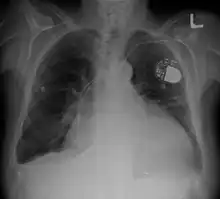

Cardiomegaly on chest X-ray with a pacemaker

• Chest X-ray: X-ray images help to visualize the condition of the lungs and heart. If the heart is enlarged on an X-ray, other tests will usually be needed to find the cause. A useful measurement on X-ray is the cardio-thoracic ratio, which is the transverse diameter of the heart, compared with that of the thoracic cage.[24] These diameters are taken from PA chest x-rays using the widest point of the chest and measuring as far as the lung pleura, rather than lateral skin margins. If the ratio is greater than 50%, pathology is suspected.[25] The measurement was first proposed in 1919 to screen military recruits. A newer approach to using these x-rays for evaluating heart health takes the ratio of heart area to chest area and has been called the two-dimensional cardiothoracic ratio.[26]

• Pacemaker: Coordinates contractions between ventricles. In people at risk of arrhythmias, drug therapy or an implantable cardioverter-defibrillator (ICD).